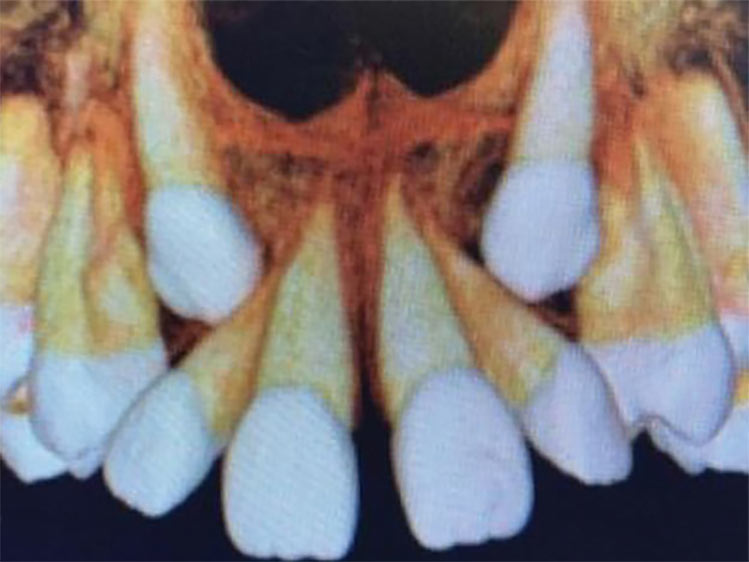

É necessário fazer uma avaliação clínica e radiográfica criteriosa da oclusão do paciente.

Nesse momento tão dinâmico da vida dos pequenos é importante acompanhar de perto as transformações, se certificando se estas mudanças estão acontecendo de forma correta.

Se algo estiver fora da normalidade, o problema poderá ser interceptado e corrigido prontamente, evitando longos tratamentos ortodônticos no futuro.